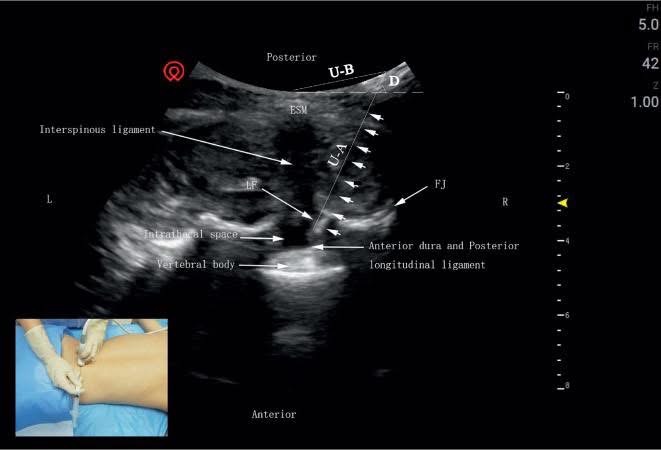

質疑 7:你們用的「針刀」到底是什麼?是不是民俗療法?

→ 回應:針刀並非傳統針灸,也非民俗療法,而是一種經過臨床驗證、具有解剖依據的「微創軟組織鬆解術」。在超音波與MRI輔助下,更能做到精準對位、不傷脊髓、不用全身麻醉,傷口甚至不用縫合因為只有0.4-0.6MM(等於0.04CM!)